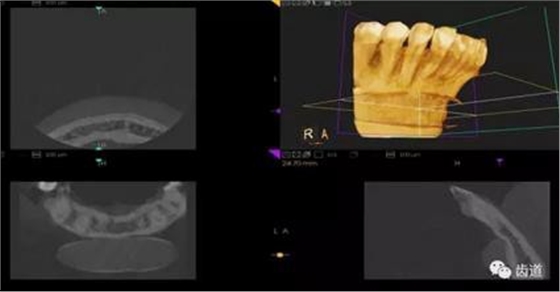

1、下頜骨種植牙前測(cè)量準(zhǔn)備影像

2、上頜骨種植牙前準(zhǔn)備影像